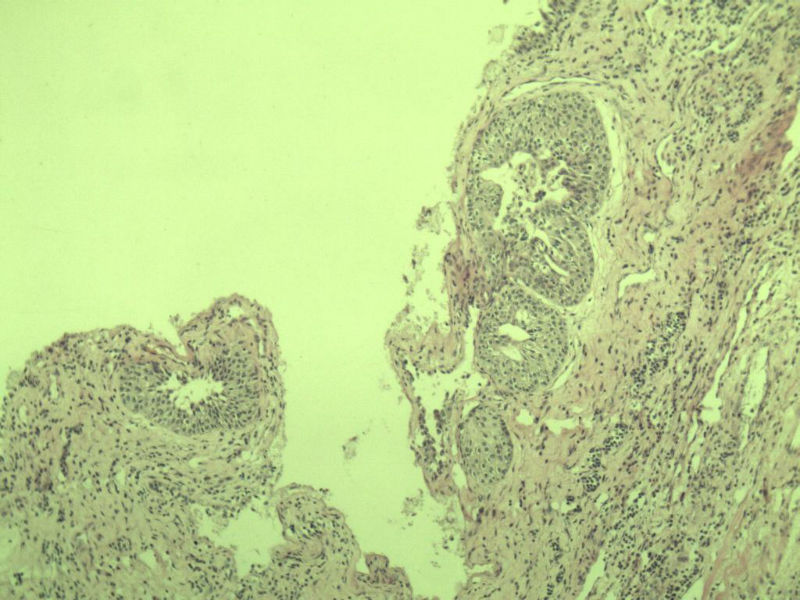

男 75岁 因排尿困难半年行前列腺切除术,体积 4 × 3 × 2.5 cm3,切面灰白,实性,质韧。请各位老师看看 有问题没? 谢谢了!

高级别上皮内瘤变,建议免疫组化:P63、34BE12、P504S

前列腺增生症伴鳞化

良性前列腺增生

良性前列腺增生伴尿路上皮化生

前列腺增生伴尿路上皮鳞化及Brown巢形成,未见恶性。